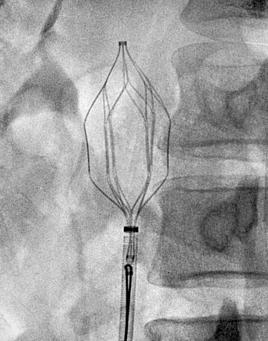

(四)血管疾病介入治疗:一桥飞架南北,天堑变通途

我科已常规开展外周血管介入手术,如对具有高危肺栓塞风险的下肢深静脉血栓形成病人,行下腔静脉滤器置入+置管溶栓术,治疗完成后行下腔静脉滤器取出,对下肢动脉缺血病人行球囊扩张+支架置入术,取得了良好的效果并积累了丰富的临床经验。